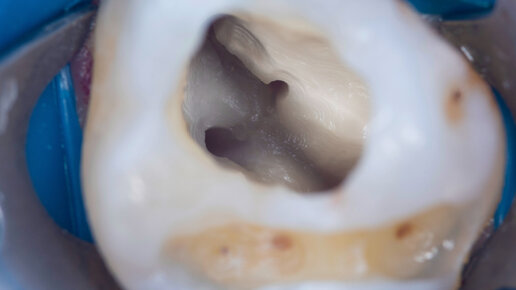

Эндо-доступ. Прохождение канала SOCO - файлами. Ирригация: Гипохлорит натрия - 3%. Пульпит - Часть 1